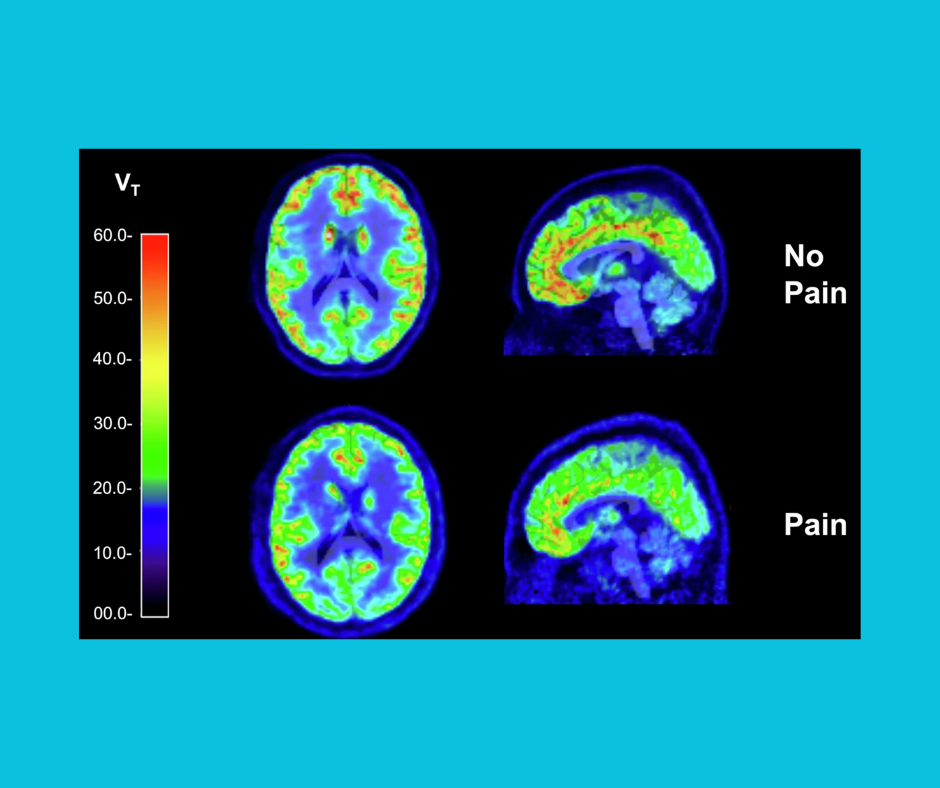

At the conference, Dr. Davis presented a talk as part of a symposium titled ‘Decoding Pain: Brain Structural and Functional Biomarkers’. This talk discussed results from her recent publication in Neuropsychopharmacology. Click here to read the full paper!

Dr. Davis also presented a poster investigating the relationship between kappa opioid receptor availability (KOR) and BPD traits. See pictures below!